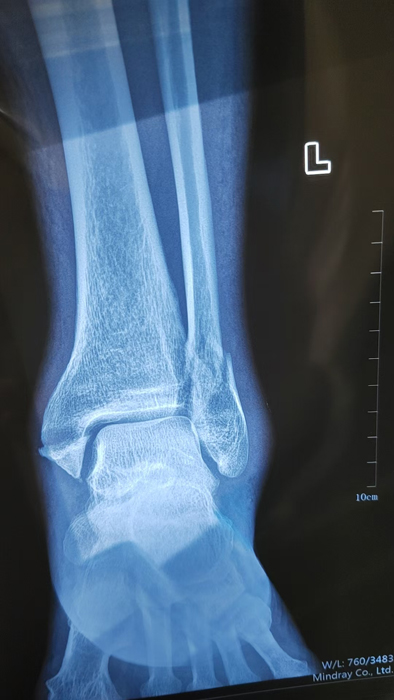

2月4日,何店鎮(zhèn)中心衛(wèi)生院接診一名左踝關(guān)節(jié)外傷患者,經(jīng)影像檢查,確診為左脛、腓骨下段骨折。外科醫(yī)生姜穩(wěn)迅速完成術(shù)前檢查及病情評(píng)估,并與患者及家屬深入溝通治療方案。在患者強(qiáng)烈要求于本院進(jìn)行手術(shù)的情況下,為最大限度保障手術(shù)質(zhì)量與安全,該院特邀請醫(yī)共體牽頭單位——曾都區(qū)人民醫(yī)院脊柱創(chuàng)傷外科專家團(tuán)隊(duì)前來指導(dǎo)。